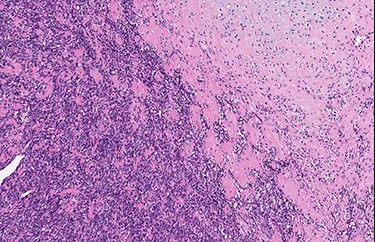

An excisional biopsy of the orbital mass was performed. We found a firm, whitish nodule that measured 2.8 × 1.9 × 1.7 cm. Microscopically, the neoplasm had a typical biphasic pattern, with a hypercellular small round cell component intermixed with islands of well-differentiated cartilage showing metaplastic bone ossification. There was an abrupt transition between the two different components of the neoplasm, and a hemangiopericytoma-like vascular pattern was noted (Figs 2–4). Immunohistochemically, the mesenchymal small cell component showed focal cytoplasmic positivity for CD99, while the cartilaginous component was S100 protein-positive (Figs 5 and 6). The neoplastic cells showed negativity for cytokeratin AE1/AE3, STAT6 (signal transducer and activator of transcription-6), CD31 and CD34. The findings were consistent with MCS. This case was sent for a second opinion to Prof. Angelo Paolo Dei Tos (Department of Pathology, Azienda ULSS 2 Marca Trevigiana, Treviso, Italy) who confirmed the diagnosis of MCS, also reporting nuclear positivity for SOX9, a master regulator of the differentiation of mesenchymal cells into chondrocytes.

Low-power view of the lesion showing central ossification (H&E).

Abrupt transition from small cell component to well differentiated cartilaginous area (H&E, high power view).